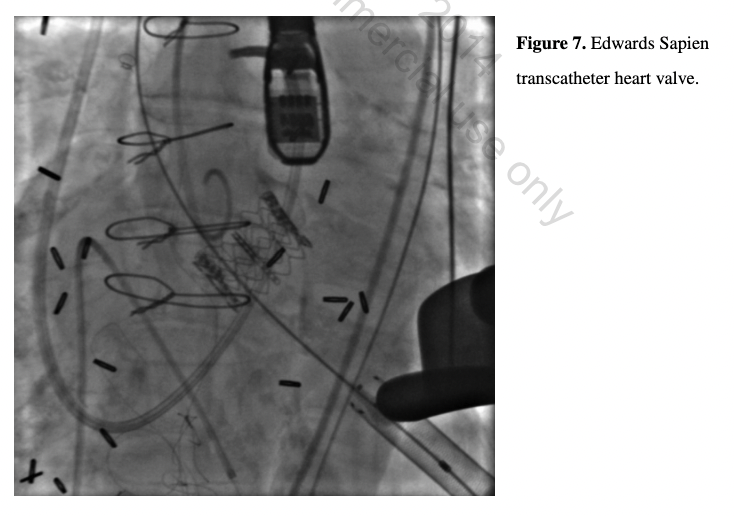

Following all testing, valve conference case review, multidisciplinary team discussions, and patient and family counseling and consent, successful and uncomplicated TAVR was performed via transapical access under general anesthesia with fluoroscopic and transesophageal imaging. Right heart catheterization, temporary RV apical pacing wire placement, and aortography were accomplished uneventfully. Thoracotomy, LV apical exposure, and ventriculotomy with Ascendra sheath placement were performed without difficulty. Balloon aortic valvuloplasty (20 mm x 3 cm Sapien balloon; Edwards Lifesciences) was undertaken with rapid pacing of 160 bpm without significant hemodynamic compromise or worsening aortic insufficiency. A 23 mm Sapien THV valve was then positioned and deployed uneventfully with rapid pacing at 180 bpm (Figure 7). The patient required no escalation in vasopressors or inotropes following device implantation and transesophageal echocardiography confirmed ideal placement with trivial paravalvular aortic insufficiency, a residual mean aortic valve gradient of 6 mm Hg, normal coronary flow, and no aortic injury.